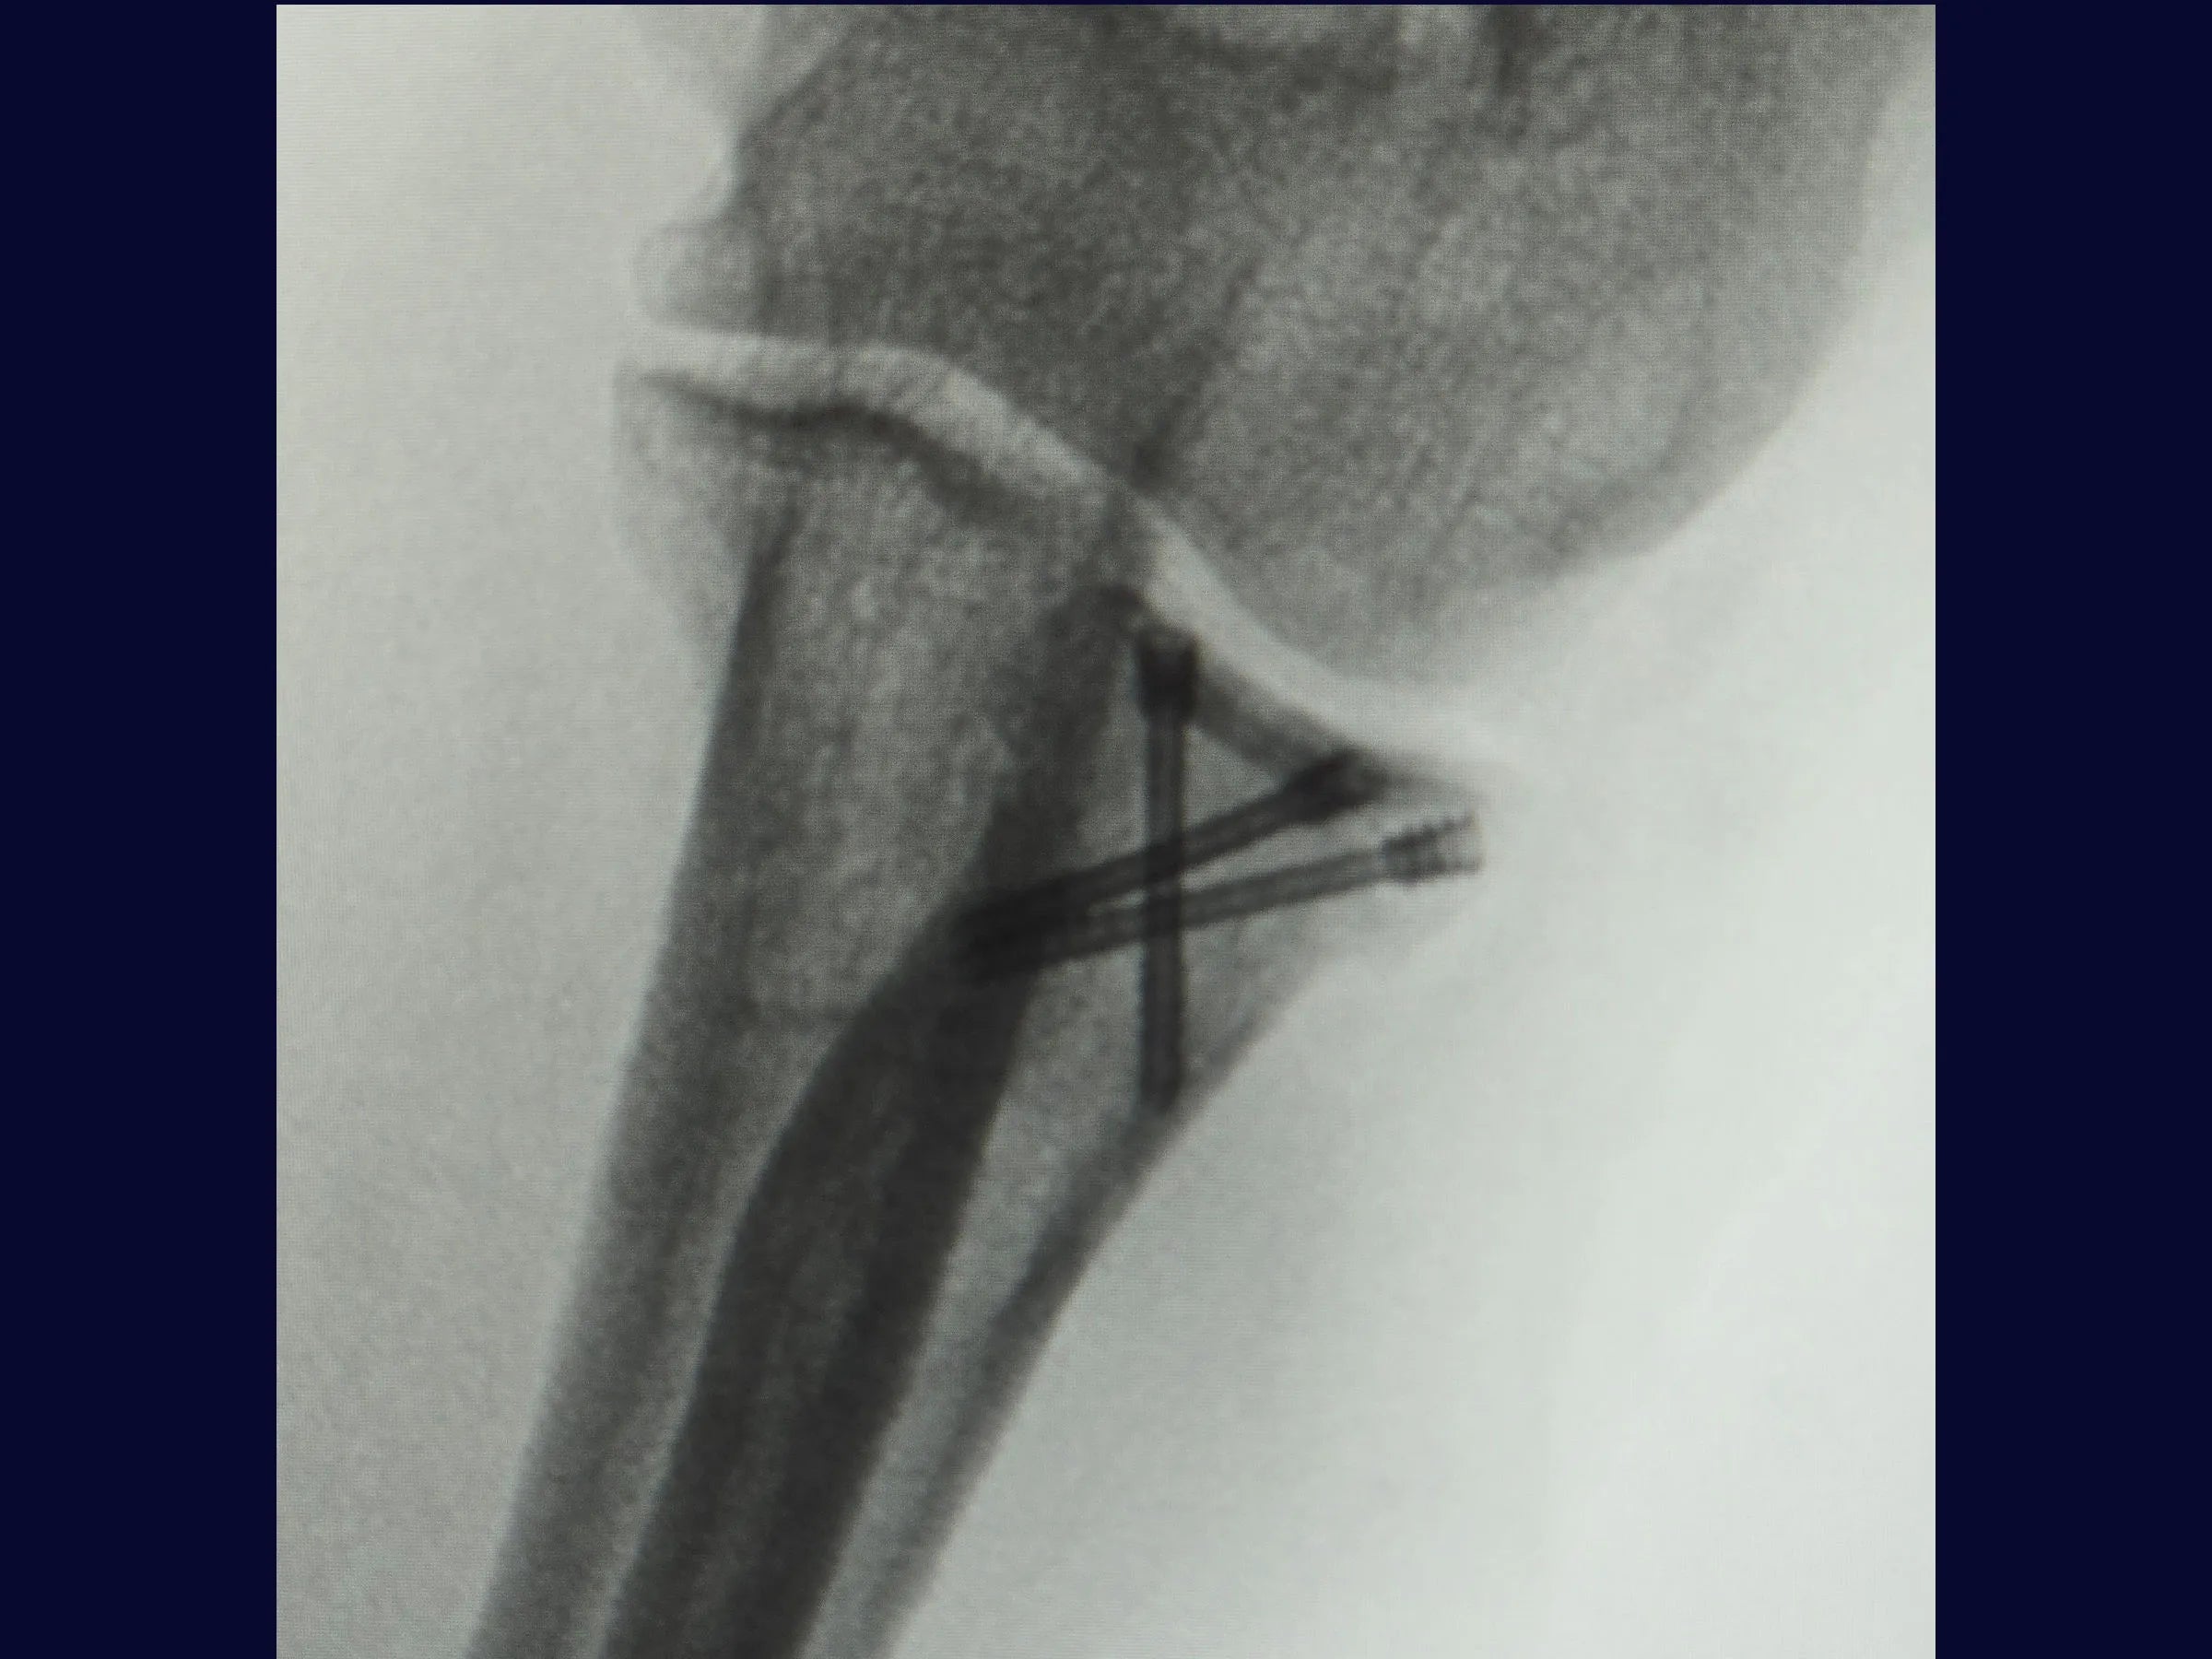

Este treinamento apresenta a técnica do tripé com parafusos de dupla compressão e reinserção capsular com âncora metálica, em vídeo 4K sob a perspectiva cirúrgica, permitindo compreender cada detalhe técnico e aplicar com segurança na prática.

- Técnica do tripé com parafusos de dupla compressão (2,4 mm).

- Fixação Segura: Parafusos sepultados em ângulo biomecânico de 45°.

- Testes de estabilidade intraoperatória e mobilidade precoce.